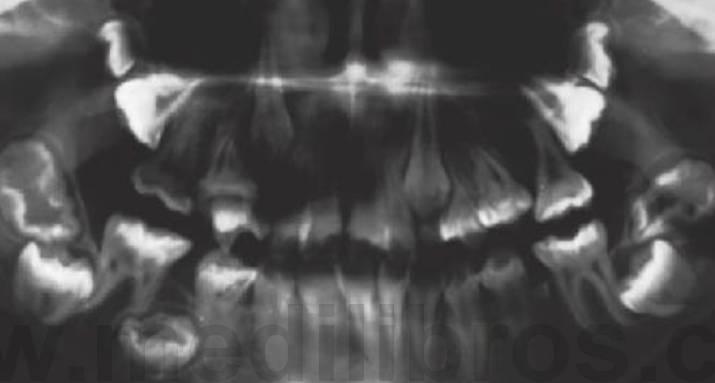

Displasia cleidocraneal (OMIM 119600)

Este trastorno se hereda con un rasgo autosómico dominante y se caracteriza por una frecuencia elevada de mutaciones espontáneas. Se ha localizado en 6p21 con mutaciones en el gen CBFA1 (fig. 9.9).

- Múltiples dientes supernumerarios (fig. 9.9A).

- Retraso en la erupción de los dientes.

- Formación de quistes dentígeros.